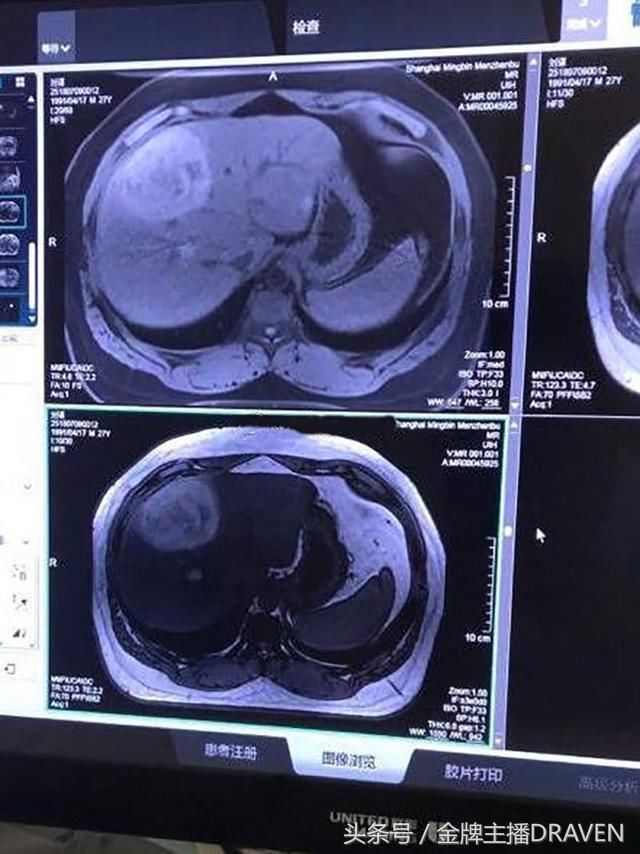

一开始,有微博大V爆料PDD入院,疑似患上了良性肿瘤。该文还强调最终诊断结果没有出来,有待进一步调查。但消息一出,就有无良小编立刻改成了“PDD患癌”,这下震惊了PDD的粉丝和电竞圈的网友们,很多人信以为真,一时间大家议论纷纷。